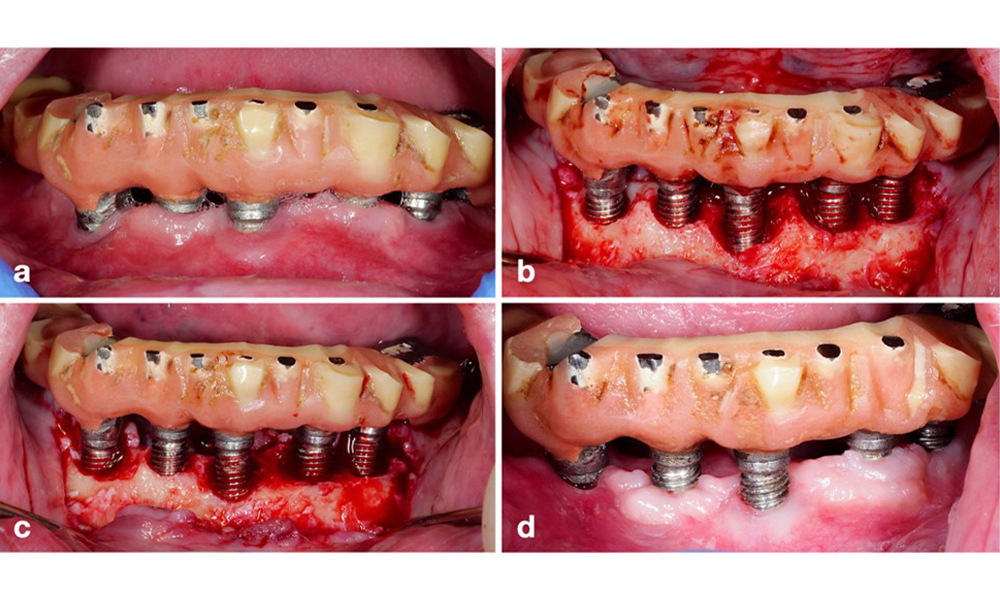

Периимплантитът се идентифицира чрез (1) признаци на възпаление, подобни на мукозит, (2) рентгенографски данни за загуба на кост след първоначалното заздравяване и (3) увеличаване на дълбочината на сондиране в сравнение с измерванията, направени малко след поставянето на протезната реконструкция (фигура 2) . При липса на предишни рентгенографии, рентгенографско костно ниво ≥ 3 mm и кървене при сондиране и дълбочина на сондиране ≥ 6 mm показват периимплантит.

Възстановяване на цяла зъбна дъга с различна степен на периимплантит при някои от имплантите. Имплантът в позиция 21 е силно засегнат с дълбочина на сондиране до 9 mm (a), кървене при сондиране и образуване на гной в периимплантния сулкус и вестибуларна фистула (b–c); рентгеновата снимка показва приблизително 50% костна загуба за импланта с периимплантит в позиция 21, докато имплантът в позиция 23 показва само ограничена костна загуба, съответстваща приблизително на това, което може да се очаква след първоначалното заздравяване за този тип импланти (d).

Фигура 2. Възстановяване на цяла зъбна дъга с различна степен на периимплантит при някои от имплантите. Имплантът в позиция 21 е силно засегнат с дълбочина на сондиране до 9 mm (a), кървене при сондиране и образуване на гной в периимплантния сулкус и вестибуларна фистула (b–c); рентгеновата снимка показва приблизително 50% костна загуба за импланта с периимплантит в позиция 21, докато имплантът в позиция 23 показва само ограничена костна загуба, съответстваща приблизително на това, което може да се очаква след първоначалното заздравяване за този тип импланти (d).

Очакваната костна загуба след първоначалното заздравяване се дължи на маргиналното костно ремоделиране и варира в зависимост от фактори като имплантна система или типа имплант. Например загуба на 1–2 mm кост обикновено се счита за „нормална“ за импланти на нивото на костта с външна връзка (фигура 2d, имплант в позиция 23).